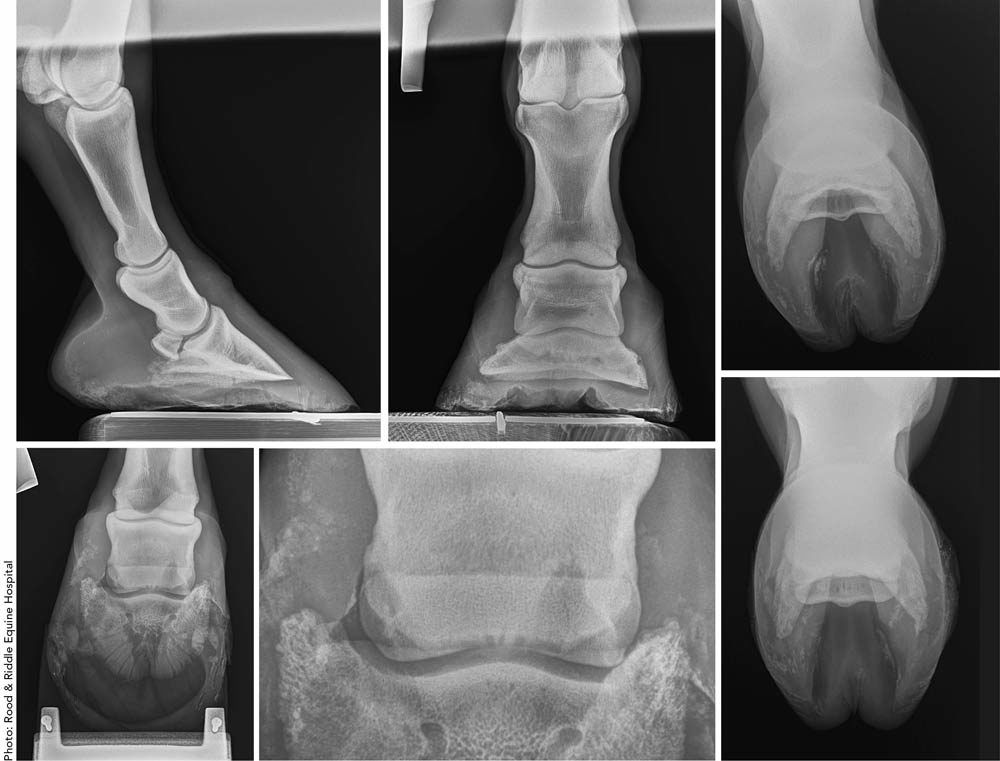

To illustrate how these differences can manifest during a specific case, we presented a case report to three farriers of differing clientele, levels of experience and service areas. We asked for their impressions, stressing what questions they would have for a veterinarian. Thank you to veterinarian and farrier Craig Lesser of Rood & Riddle Equine Hospital in Lexington, Ky., for providing this case summary.

This case involved a 12-year-old Thoroughbred gelding used as a 3-day event horse. The owner complained of the horse exhibiting chronic, progressive soreness in the right forefoot. The report notes were shared with the farriers (with the descriptions left as entered by Lesser).